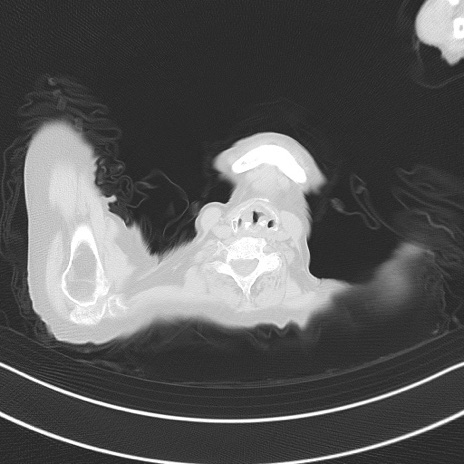

症例40(横断像)他院1日前

横断像

他院CT